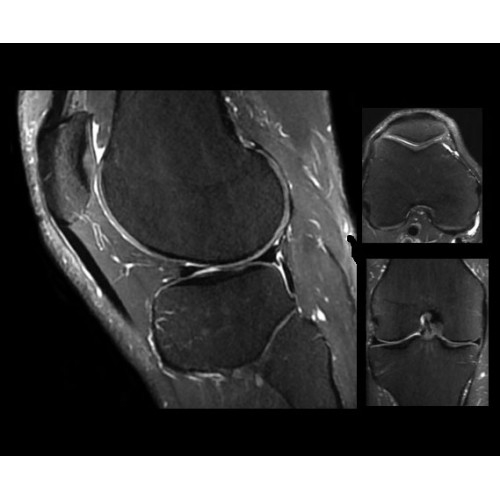

Компания GE Healthcare представляет революционную, полностью интегрированную систему SIGNA PET/MR1, в которой сочетаются времяпролетная технология (TOF) и возможности напряженности магнитного поля 3.0 Тл. Мы поможем вам поднять исследования на более высокий уровень. SIGNA PET/MR позволяет достичь впечатляющей точности и скорости исследований, а благодаря новейшей технологии реконструкции Q.Clear2 качество изображений улучшается в два раза. Кроме того, в систему включен полный набор клинических приложений и гибких катушек для проведения любых видов исследования, открывая для вас возможности визуализации, о которых вы даже не догадывались.

• Q.Clear — в основу технологии легли накопленные знания о том, как минимизировать помехи при реконструкции и получить четкое изображение. При значительном улучшении качества изображения сохраняется точность расчетов. Сочетание технологии TOF и реконструкции Q.Clear — ваш надежный помощник для получения точных и достоверных данных.

Стандартный пакет приложений SIGNA Works позволит вам достичь желаемых результатов в клинической практике благодаря набору высокоэффективных средств визуализации. Программные приложения, входящие в состав данных клинических пакетов, включают широкий спектр контрастов, функции обработки 2D- и 3D-данных, а также возможность коррекции артефактов движения. SIGNA Works предоставляет набор инструментов, необходимых для проведения эффективного клинического исследования.